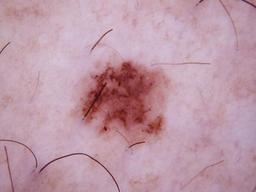

Training set from the ISIC 2018 Challenge.

[1] Noel Codella, Veronica Rotemberg, Philipp Tschandl, M. Emre Celebi, Stephen Dusza, David Gutman, Brian Helba, Aadi Kalloo, Konstantinos Liopyris, Michael Marchetti, Harald Kittler, Allan Halpern: "Skin Lesion Analysis Toward Melanoma Detection 2018: A Challenge Hosted by the International Skin Imaging Collaboration (ISIC)", 2018; arxiv.org/abs/1902.03368

[2] Tschandl, P., Rosendahl, C. & Kittler, H. The HAM10000 dataset, a large collection of multi-source dermatoscopic images of common pigmented skin lesions. Sci. Data 5, 180161 doi:10.1038/sdata.2018.161 (2018).